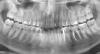

Sergun2010 Опубликовано 20 июня, 2011 Поделиться Опубликовано 20 июня, 2011 В пятницу немного отекла щека.Было подозрение на четвёрку слева сверху. Так как зуб немного болезненно реагировал на нажатие.В субботу сходил к стоматологу. В зубе стояла старая пломба. Врач после осмотра сказал, что пломба "просела" и вокруг неё образовался кариес. И есть два варианта: 1) что под пломбой кариес и нужно лечить каналы; 2) что под пломбой здоровый зуб, и нужно удалить кариес вокруг пломбы и поставить новую. Убрав старую пломбу, стоматолог сказал, что ткани под пломбой плотные, кариеса нет и вскрывать каналы не надо. Поставил новую пломбу.Сделали снимок, и причин опухоли щеки в зубах не нашли.Опухоль до сих пор не спала.В чём может быть причина? Может всё-таки в зубах? Ссылка на комментарий

Scrabble Опубликовано 20 июня, 2011 Поделиться Опубликовано 20 июня, 2011 (изменено) Синусит слева может быть. Прицельный снимок 24 сделайте. Изменено 20 июня, 2011 пользователем Scrabble Ссылка на комментарий